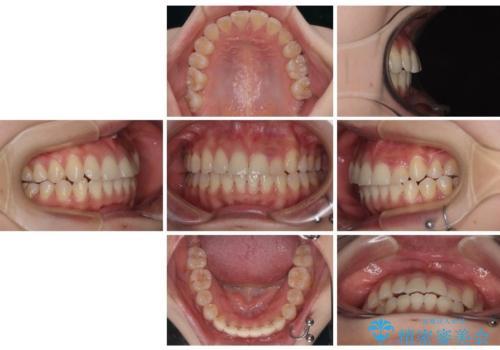

急速拡大装置 狭い上顎歯列を改善して、八重歯を改善した片側抜歯矯正治療

- 治療期間

- 1年8ヶ月

- 左上の前歯のがたつきを主訴に来院された患者様です。

上顎歯列が下顎の歯列に対して狭小であり、一部下顎の奥歯が上顎よりも外側に位置している状態でした。

上顎の歯列を拡大しスペースを設け、さらに左上の小臼歯を一本抜歯し左上の八重歯を歯列内に入れ整えていくことにしました。